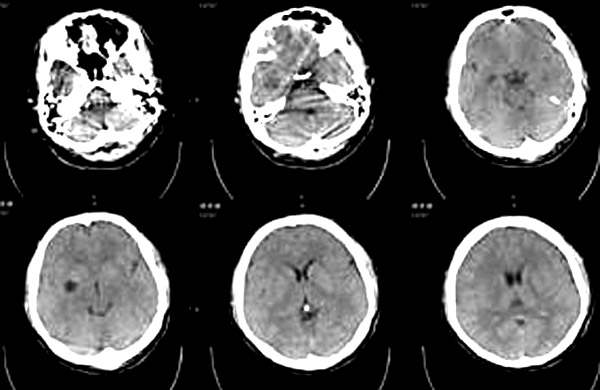

患者男,21岁,外伤时发现右侧基底节区有低密度影,问了既往史,无异常